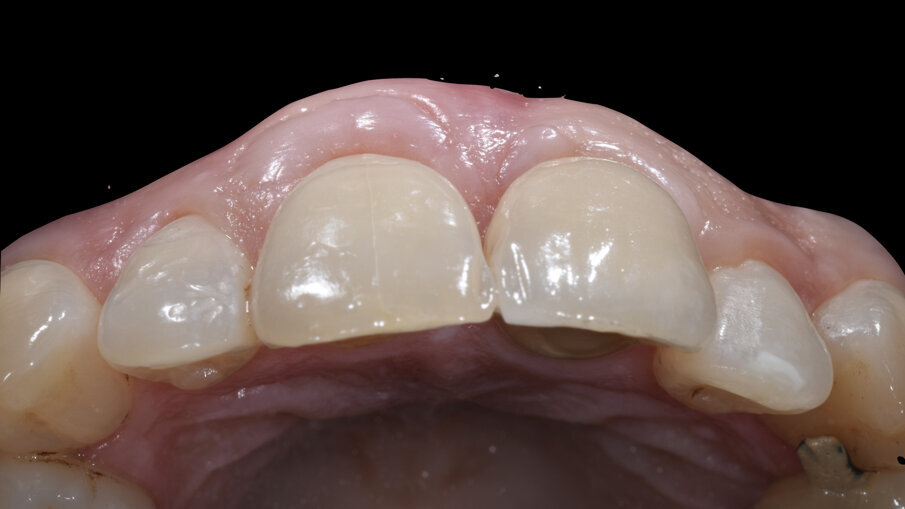

All’esame obiettivo generale la paziente presenta una malocclusione di 2a classe con recessioni multiple dei settori frontali e lateroposteriori, un sorriso gengivale e un fenotipo gengivale sottile e festonato con denti di forma triangolare, mentre a livello locale il dente 1.1 si presenta fortemente discromico con fistola apicale, recessione dei tessuti molli sia del 1.1 che del 2.1 di circa 3 mm con erosione cervicale (Fig. 2). Una prima indagine radiografica bidimensionale (rx endorale periapicale) evidenzia sul 1.1 una terapia canalare incongrua e radiotrasparenza apicale. Un esame tridimensionale CBCT evidenzia la discontinuità della corticale vestibolare identificata come classe 4 secondo Tarnow4, come esito dell’infezione apicale, ma rimane un ponte osseo crestale che sarà fondamentale per il percorso di ricostruzione dei tessuti duri e molli (Fig. 3).

Dopo un full fotografico completo, l’analisi dei fattori di rischio estetici, clinici e radiografici ha identificato la necessità di procedere all’estrazione dell’1.1 e sua sostituzione con una riabilitazione implantoprotesica secondo un timing e un protocollo di post estrattivo di tipo 3: estrazione, gestione dei volumi ossei e gengivali e a distanza di 4/5 mesi posizionamento dell’impianto3.